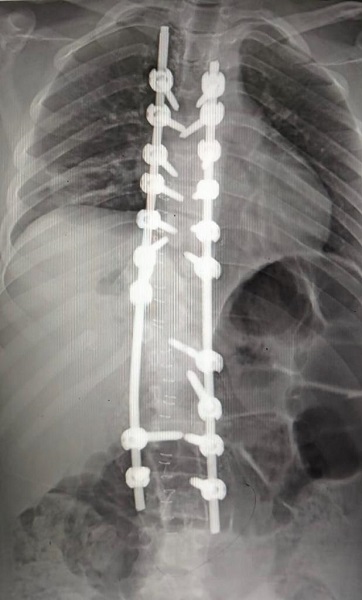

أعلن الدكتور منصور حسن رئيس جامعة بني سويف، اليوم، نجاح فريق من قسم جراحة المخ والأعصاب بمستشفيات بني سويف الجامعية، في إجراء جراحة دقيقة والتي تعد العملية الخامسة لإصلاح تشوه واعوجاج بالعمود الفقري داخل القسم، ومن أصعب واعقد عمليات العمود الفقري لفتاة في العشرينات من عمرها نتيجة عيوب خلقية بالعمود الفقري.

وأوضح رئيس جامعة بني سويف، أنه تم إجراء العملية الجراحية بدقة عالية وخرجت المريضة في صحة جيدة لاستكمال العلاج بقسم جراحة المخ والأعصاب واستعاده القوة العضلية، موجهًا الشكر إلى الدكتور وائل صقر عميد كلية الطب ورئيس مجلس إدارة مستشفيات جامعة بني سويف، والدكتور محمد شعبان أبو العلا المدير التنفيذي لمستشفيات جامعة بني سويف وأستاذ جراحة المخ والأعصاب، من خلال السعي الدائم لتقديم خدمة طبية متميزة ولرفع المعاناة عن المرضى داخل المحافظة والمحافظات المجاورة.

شارك في إجراء العملية فريق طبي من قسم جراحة المخ والأعصاب برئاسة الدكتور محمد شعبان المدير التنفيذي لمستشفيات بني سويف الجامعية وأستاذ جراحة المخ والأعصاب، والدكتور حسام مصطفي مدرس جراحة الأعصاب بالقصر العيني واستشاري إصلاح تشوهات العمود الفقري والدكتور ياسر محمد، والدكتور هاني محمد والدكتور محمود رمضان، والدكتور ماجد الجبالي مدرس جراحة الأعصاب، والدكتور عبد الرحمن صابر مدرس مساعد جراحة المخ والأعصاب، ومسؤولي وحدة جراحة التشوهات بالعمود الفقري.